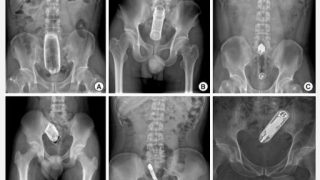

尿道や膀胱から摘出された驚くべきもの7選!自慰や性的虐待で起こる「尿道異物」

尿道の内部に本来は存在しないものが入り込んでしまうことを「尿道異物」といいます。好奇心や性的な目的で自ら挿入するケースが多くみられます。

アナルから大人のおもちゃが抜けない!肛門性交や自慰で起こる「直腸異物」とは?

性行為や自慰によって肛門から大人のおもちゃや野菜などを挿入し、それを取り出せなくなることがあります。そんな「直腸異物」の症例を紹介します。